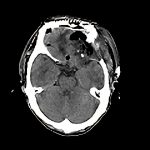

髄膜腫

(嗅溝部)

断層撮影

手術前1

手術後

No.’12_147 手術前1

No.’12_147 手術後